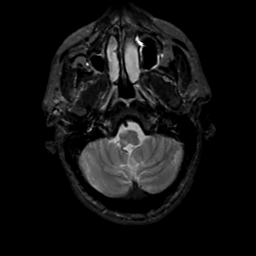

MR Study #15, June 9, 1991 -- Slice #7

[Home][Help][Clinical][Tour 1][Tour 2] Slice 7